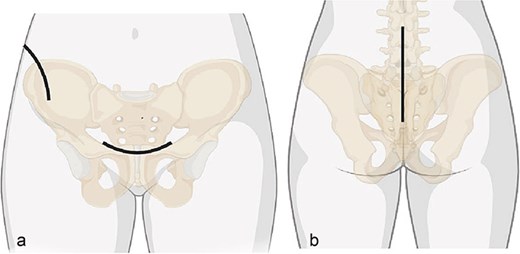

Surgical approaches diagram: (a) anterior approach; (b) posterior approach.

After one week of monitoring in the ICU, where she remained stable without need for ventilatory support, the patient was transferred to the ward. She then underwent the first surgical stage in supine position. Anterior pelvic fixation (Fig. 3a) was performed via a Pfannenstiel anterior approach combined with the first window of the right ilioinguinal approach, using a 3.5-mm reconstruction plate on the right anterior column crossing the pubic symphysis and a 3.5-mm retrograde screw in the left anterior column, inserted through the same Pfannenstiel access. During the same procedure, a 7.3-mm trans-sacral screw was placed in S1 on the right to stabilize the sacral fracture (Fig. 4). The surgery lasted ⁓3 h, and the patient was transferred to the semi-intensive care unit for postoperative monitoring.

The two-stage approach addressed initial severity (Fig. 3), using a Pfannenstiel and ilioinguinal approach for anterior fixation and an S1 trans-sacral screw for sacral stability [10, 11], followed by lumbopelvic fixation for posterior stability [12]. A 3-week delay, partly due to material unavailability, caused fibrosis, complicating reduction [13]. Seroma drainage in the second stage mitigated infection risks from the Pfannenstiel approach. ICU monitoring reflected management complexity despite stability [14]. Follow-ups over 18 months demonstrated functional recovery, quality-of-life gains, and psychological stability by 6 months, sustained to 18 months (Table 2, Fig. 7), despite early anxiety; this contrasts with studies linking severe psychological distress to poorer outcomes in Tile C fractures, suggesting early intervention mitigated these risks [5]. The Majeed score’s specificity, despite lacking a Portuguese version, and SF-12 supported outcomes analysis [15]. Pain assessment via the Numeric Pain Scale (NPS) revealed persistent lumbar pain radiating to right lower limb until the 4th week (NPS 4), resolving significantly by 3 months (NPS 1) and absent thereafter (Table 2, Fig. 7), consistent with rehabilitation progress and lumbopelvic fixation stability. This case underscores surgical timing challenges, the impact of delayed fixation, and multidisciplinary care’s value.